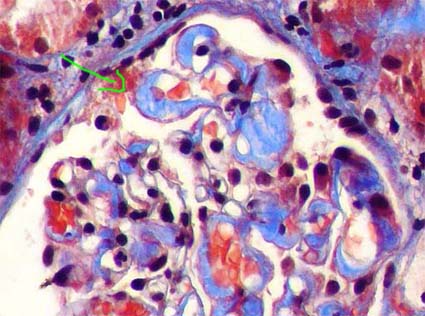

Figure 7. Tubular casts in myeloma kidney. Usually they are rigid and refractile. With trichrome stain they can be seen red or green (or blue according to the used technique). Many of them are accompanied by cells (see Figures 8 and 9). (Gomori’s trichrome, X400).

Figure 8. In this microphotography we can see two cylinders of amorphous material surrounded by multinucleated giant cells. This aspect is very suggestive of myeloma kidney (or cast nephropathy). (Masson’s trichrome, X400).